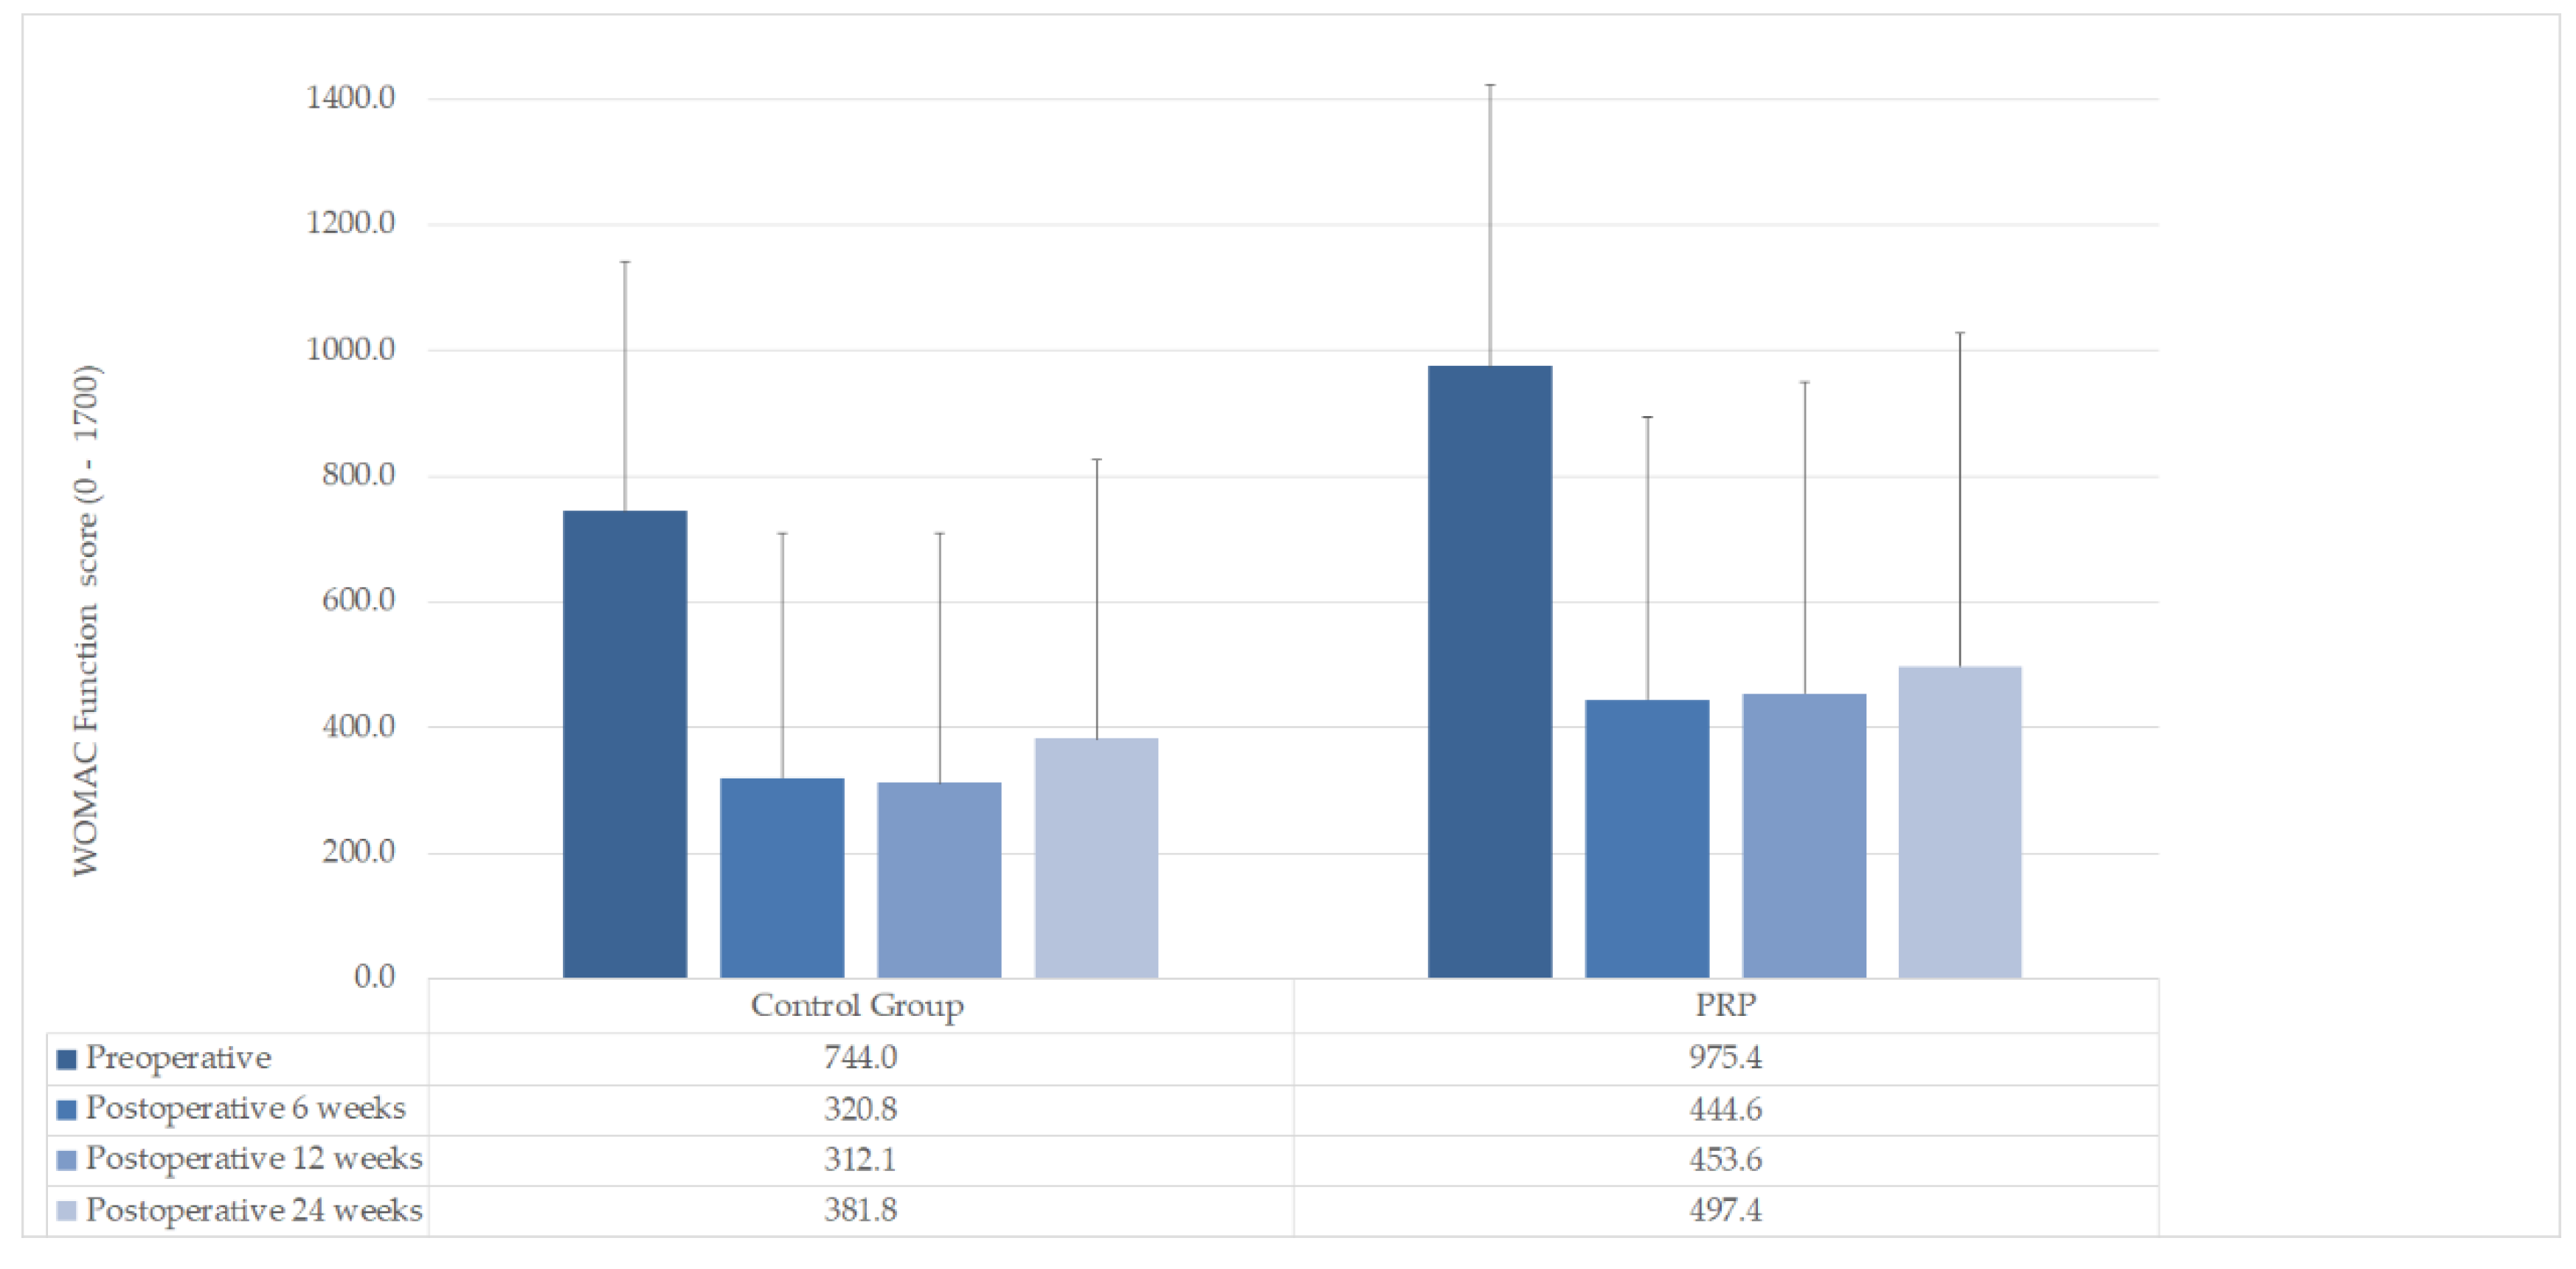

| WOMAC Function mean (±SD) | |||

| Preoperative | 975.4 (±449.2) | 744.0 (±397.2) | n. s (p = 0.178) |

| Postoperative 6 weeks | 444.6 (±449.2) | 320.8 (±387.9) | n. s (p = 0.462) |

| Postoperative 12 weeks | 453.6 (±495.9) | 312.1 (±397.4) | n. s (p = 0.435) |

| Postoperative 24 weeks | 497.4 (±530.4) | 381.8 (±444.9) | n. s (p = 0.556) |